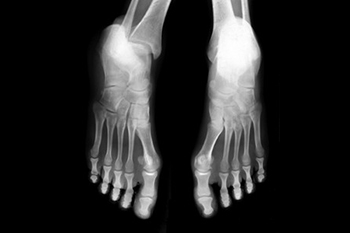

Understanding Lisfranc Injuries

A Lisfranc injury affects the middle part of the foot, where the long bones of the toes connect to the arch. This type of injury can happen during sports, a misstep on uneven ground, or from a heavy object falling on the foot. A Lisfranc injury may involve stretched ligaments or broken bones, depending on how serious the impact is. Common signs include swelling on the top of the foot, bruising on the bottom of the arch, and pain that makes it hard to walk or put weight on the foot. These injuries are often mistaken for a simple sprain, but if left untreated they can lead to arthritis, ongoing pain, or changes in foot shape. A podiatrist can check for a Lisfranc injury with an exam and imaging tests, and recommend the right treatment, which may include immobilization or surgery. If you have symptoms of a Lisfranc foot injury, it is suggested that you make an appointment with a podiatrist for an exam and treatment.